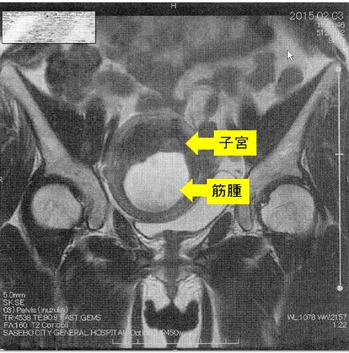

´ÁÊýÌô¤Ç»ÒµÜ¶Ú¼ð9Ѥ¬7ѤËÀ¸ÍýÄˤâ¿Î̽зì¤â²þÁ±¼ê½Ñ²óÈò¤Ç¤¹¡£¶Ú¼ð¤ÎMRI¼Ì¿¿¤Ç¤¹

¡Ú2015ǯ2·î3Æü¡¡£Í£Ò£É¼Ì¿¿¡Û

¢¨Çò¤¤Éôʬ¤¬¶Ú¼ð¡¢¼þ¤ê¤ÎÉôʬ¤¬»ÒµÜ¤Ç¤¹¡£